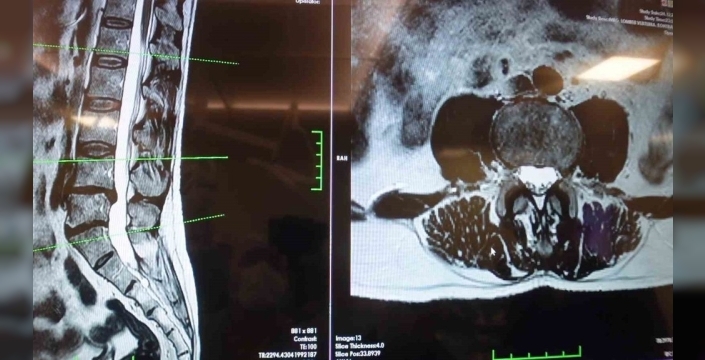

Elazığ Fırat Üniversitesi Hastanesi Beyin ve Sinir Cerrahisi Anabilim Dalı Başkanı Prof. Dr. Fatih Serhat Erol, bel fıtığı ve mekanik bel ağrıları hakkında önemli bilgiler paylaştı.

Ayrıca, omurilik kanal darlığı olan hastaların da önemli bir grup oluşturduğunu belirten Erol, bu durumun dejeneratif süreçler sonucunda oluştuğunu ve tedavi sürecinin doğru tanıya göre belirlendiğini açıkladı. Hastaların mutlaka bir uzmanla görüşmesi gerektiğini vurguladı.